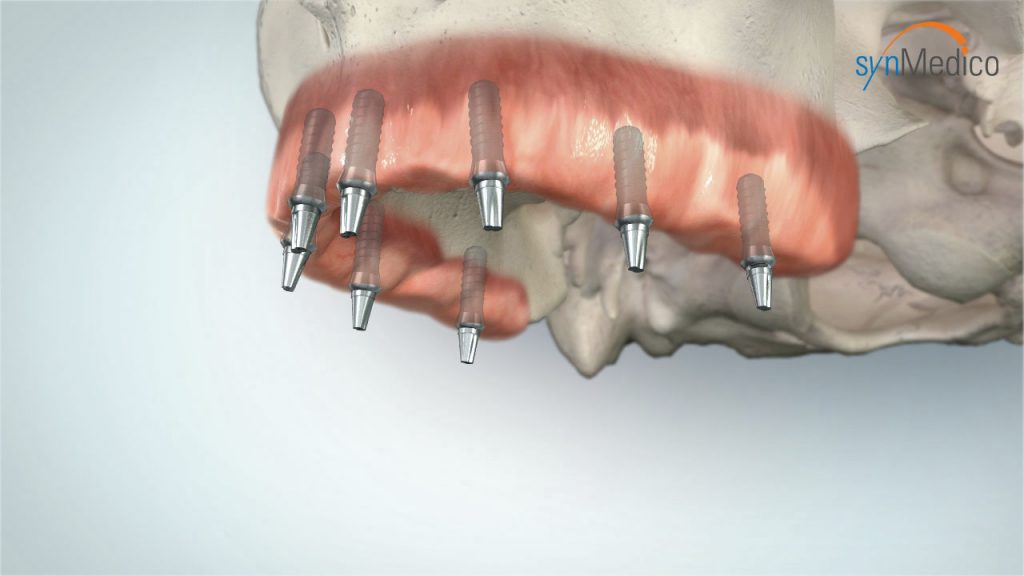

Zahnloser Kiefer

Auch ein zahnloser Kiefer kann mit Implantaten komfortabel versorgt werden. Bereits bestehender Zahnersatz gewinnt auf Implantaten neuen, verbesserten Halt. Das Gesichtsprofil bleibt erhalten, Essen und Lachen ist kein Problem mehr, die Aussprache wird deutlicher. Der Patient kann sich auf einen wirklich funktionierenden Zahnersatz verlassen.